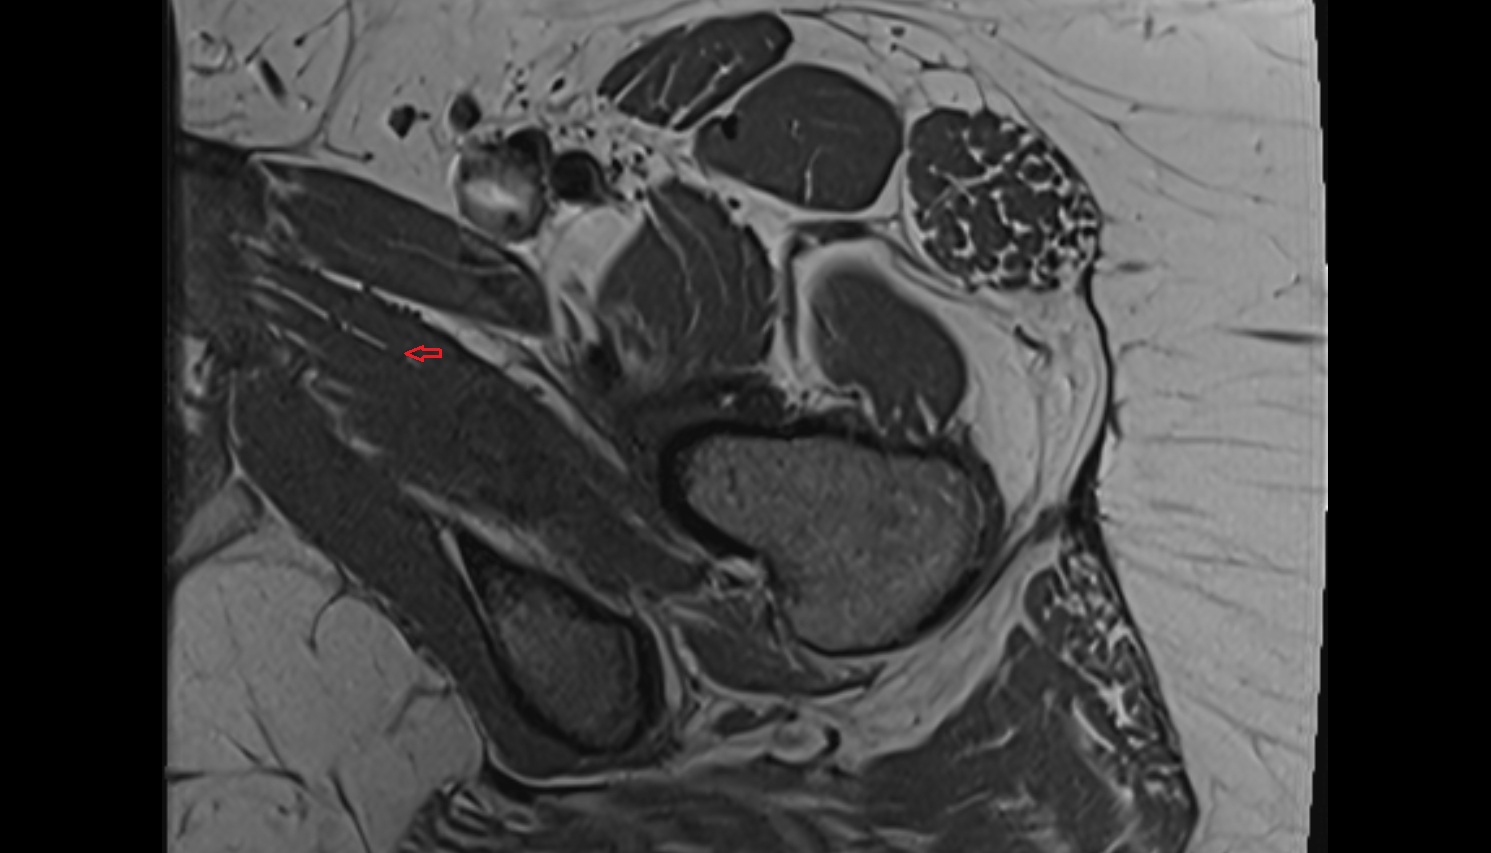

- Heart

- Left ventricle

- Right atrium

- Left atrium

- Right ventricle

- Interventricular Septum

- Left atrioventricular valve (mitral or bicuspid valve)

- Right atrioventricular valve (tricuspid valve)